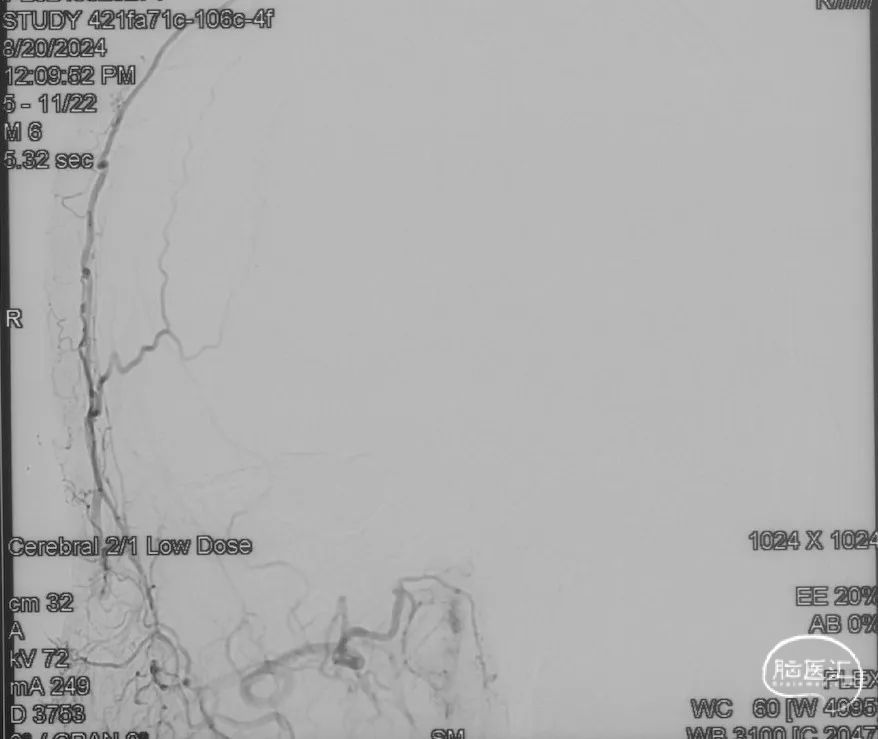

L-ECA正侧位未见向瘘口供血

双侧颈外、颈内动脉正侧位造影瘘口均不显影

双侧椎动脉造影未见瘘口显影,可见广泛皮层静脉瘀滞